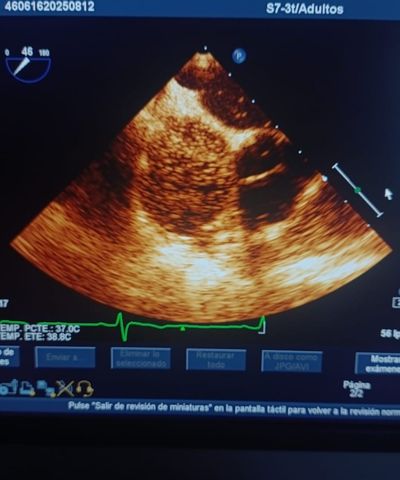

Ecocardiograma con Burbujas

Es un ultrasonido cardiaco con aplicación de burbujas para lograr un efecto de contraste en la imágen. Está indicado en sospecha de algun defecto congénito.